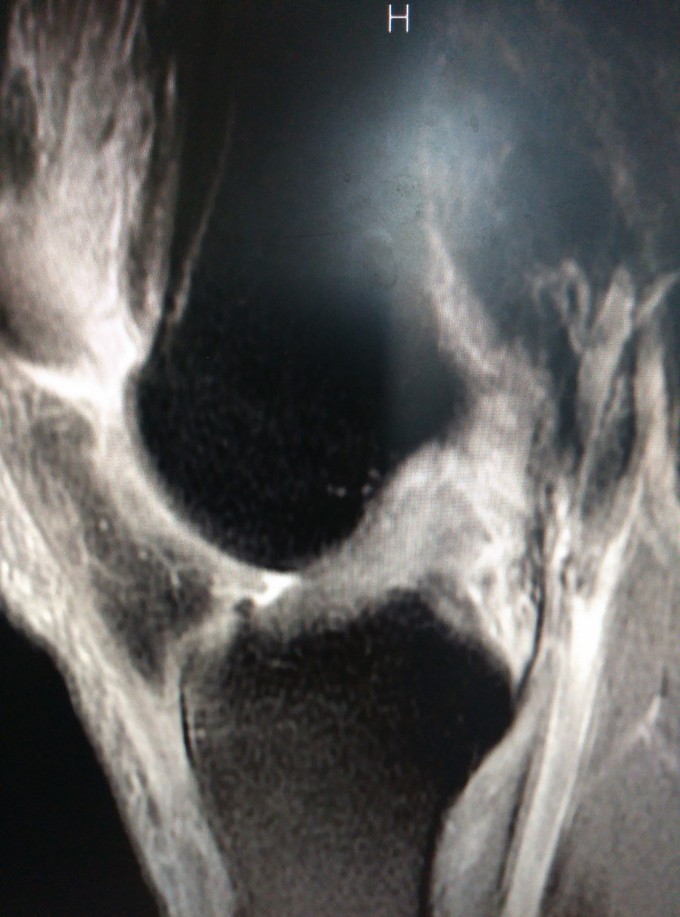

主诉:左侧膝关节扭伤后致疼痛肿胀6月余 病史:患者于6月前扭伤后膝关节肿胀疼痛,活动受限。X片未见明显骨折。于家中休养半年。今走路时觉膝关节不稳,频繁打软腿。于我院行MR检查,提示ACL损伤

查体:患肢皮温正常,左膝关节屈伸活动正常。内外侧应力试验(-) 前抽屉(+) 后抽屉(-) 辅查: MR检查提示acl断裂

断: 膝关节前十字韧带损伤 治疗:关节镜下前十字韧带重建术